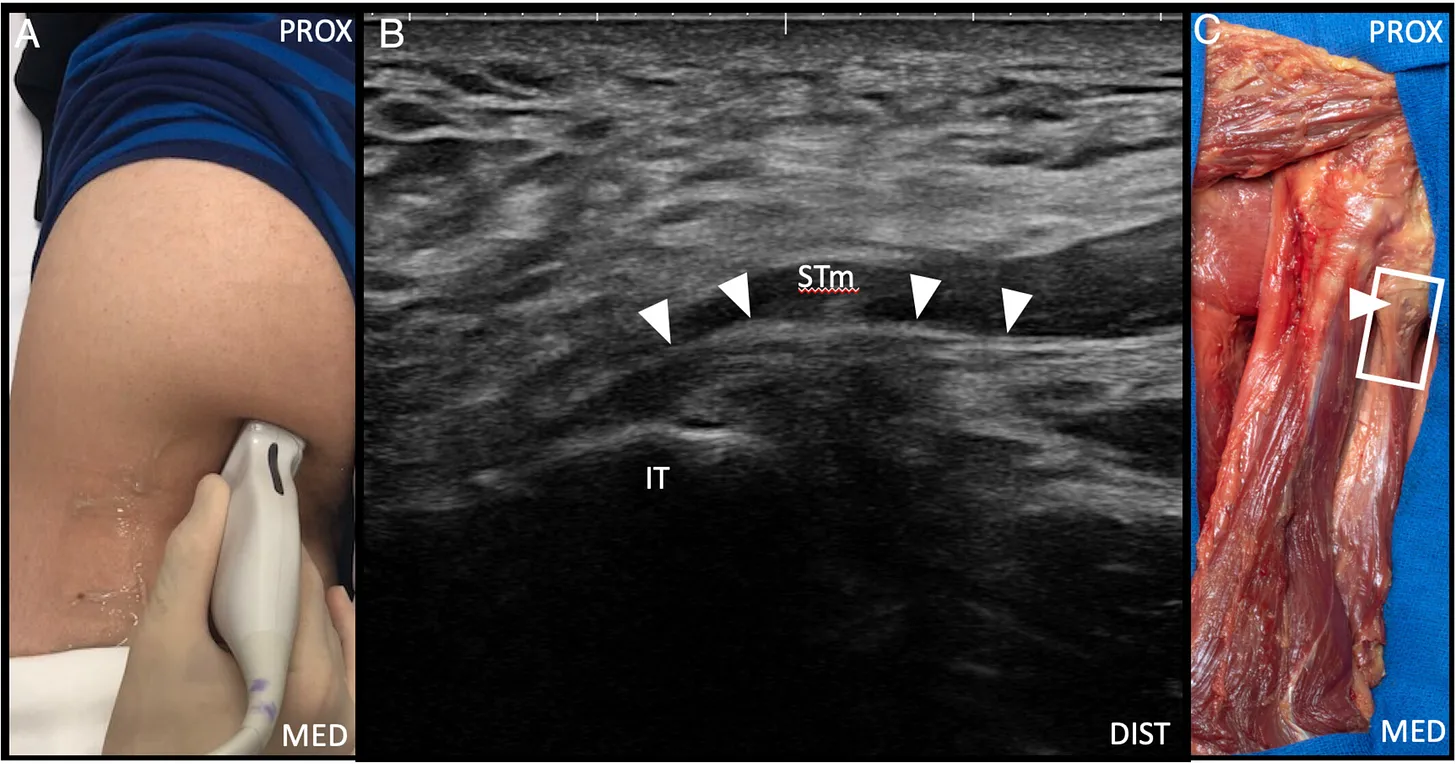

A. Posición anatómica del transductor ecográfico para la visualización en eje largo del tendón de origen isquiocondíleo proximal del aductor mayor.

B. Imagen ecográfica en vista longitudinal del tendón de origen isquiocondíleo proximal del aductor mayor (puntas de flecha). El aspecto medial del músculo semitendinoso (STm) se sitúa superficial al tendón de origen isquiocondíleo del aductor mayor.

C. Preparación cadavérica que muestra la posición del transductor para obtener la imagen en eje largo del tendón de origen isquiocondíleo proximal del aductor mayor.

IT: tuberosidad isquiática;

MED: medial; PROX: proximal;

rectángulo: posición del transductor.